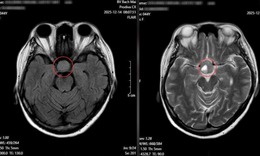

Cứu sống bệnh nhân vỡ động mạch chủ bụng bằng Stent graft

Y tế - 10/10/2025 14:54SKĐS - Vừa qua, các bác sĩ Bệnh viện Hữu Nghị đã cứu sống một bệnh nhân 76 tuổi bị vỡ túi phình kích thước gần 8cm (động mạch chủ) bằng kỹ thuật can thiệp nội mạch hiện đại, đây là một tình trạng cấp cứu y khoa có tỷ lệ tử vong cao.